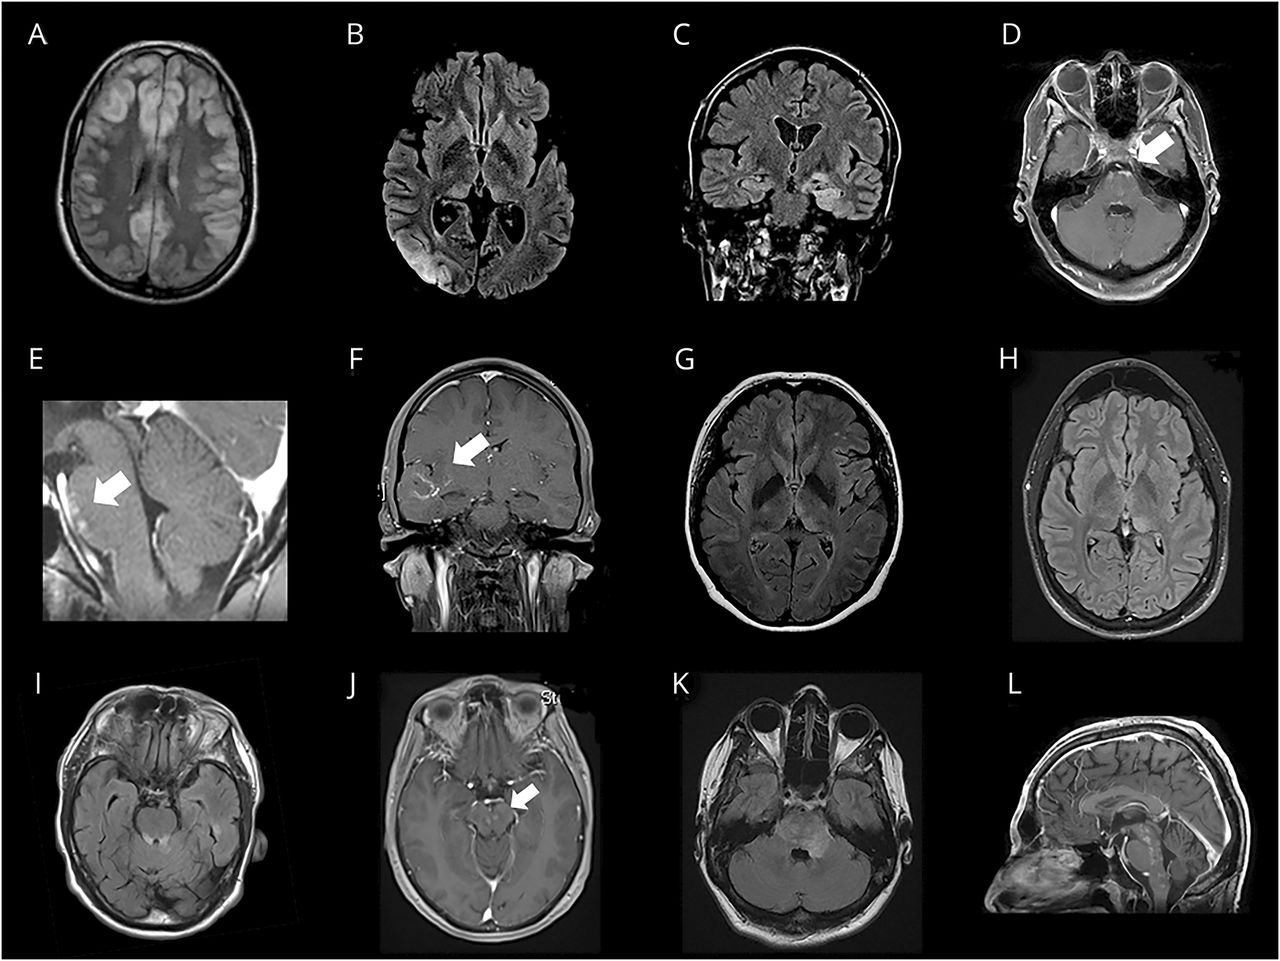

我们没有确定一个具体的放射模式MOG-Ab组相比AQP4-Ab组(n = 22)。然而,病变位于丘脑和脑桥被更频繁地出现在MOG-Ab集团(p= 0.031,p分别为= 0.007),而在延髓病变区域postrema更经常观察AQP4-group (p= 0.004,p分别为< 0.001)(表2)。其他发现皮质参与8(16.3%)和leptomeningeal增强3例(6.1%)患者。代表病例病理脑MRI显示图1。和皮质参与病人的描述特征出现在表格e - 3,links.lww.com/WNL/A473图e - 3,links.lww.com/WNL/A472。

(A, B)双边和单边皮质病变在天赋序列。(C) Temporomesial皮质病变模仿边缘脑炎天赋序列。(D-F)桥的皮质leptomeningeal钆增强。(G, H)丘脑病变天赋序列。(i (k)脑干病变涉及脑桥和中脑被盖。(左)“盐和胡椒”脑干CLIPPERS-like成像模式。图像(B)和(C)对应于同一病人在疾病的不同阶段(病人2表e - 3links.lww.com/WNL/A473)。快船=慢性淋巴细胞炎症与桥的血管周的增强对类固醇;天赋= fluid-attenuated反转恢复;MOG-Ab =髓少突细胞糖蛋白抗体。